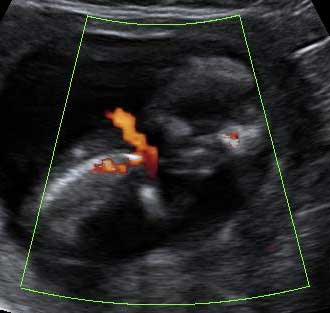

Así se ve un feto de 12 semanas de embarazo en una ecografía en 2D y en un ultrasonidos en 3D. En ambas se distingue los brazos y las piernas.

Podemos ver el bebé de 12 semanas de gestación en una imagen de dos dimensiones (a la izquierda, tumbado) y en tres dimensiones (a la derecha y en posición vertical). Las extremidades del feto (brazos y piernas) son visibles en ambos exámenes ecográficos.